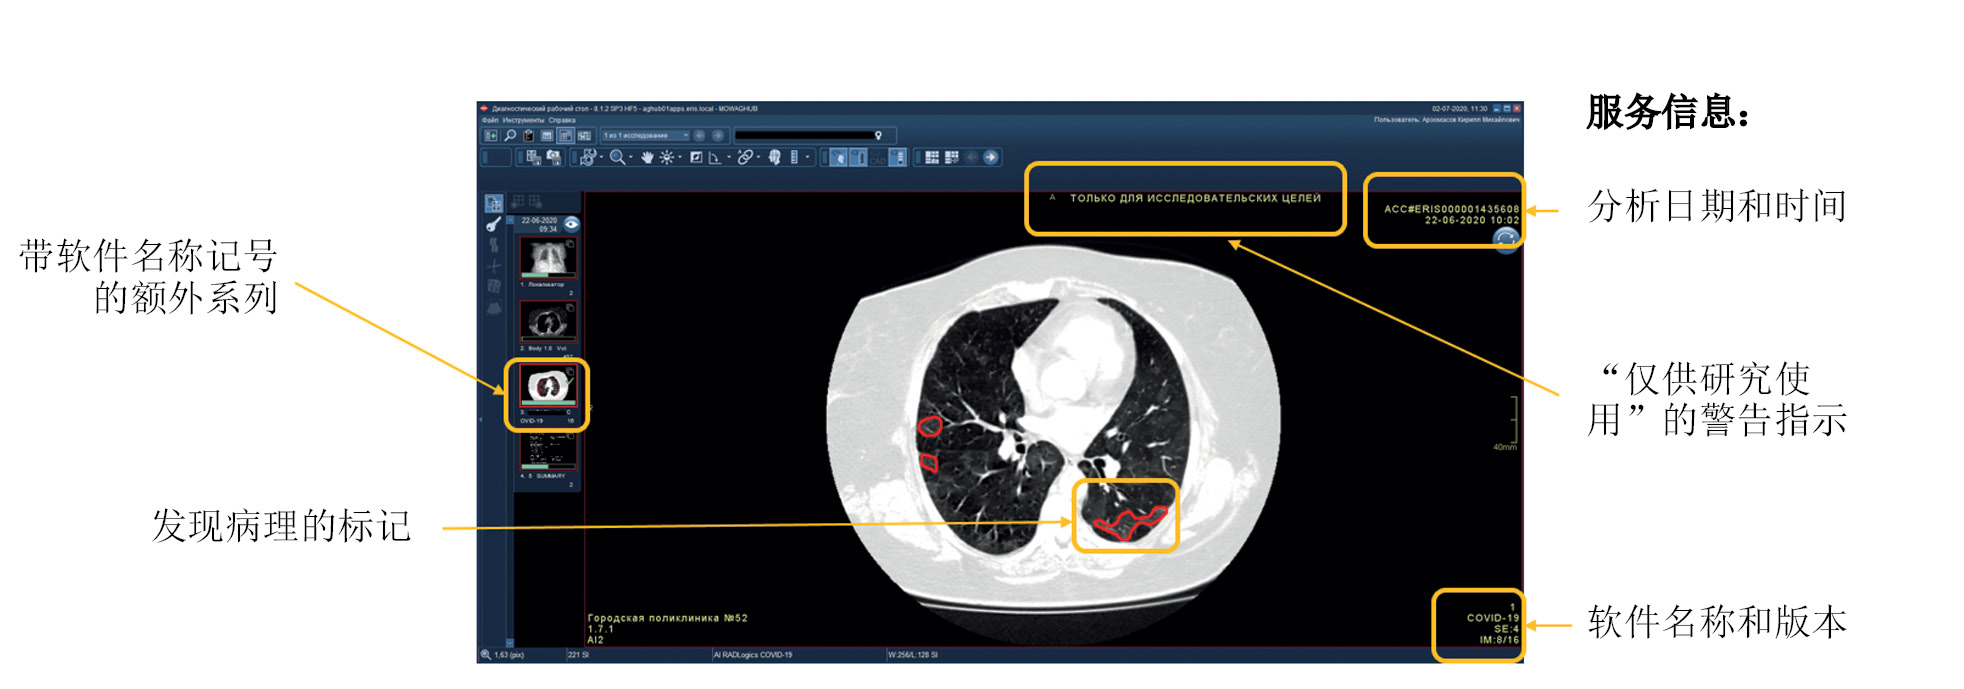

Functional testing is a stage wherein software functions specified by a supplier are checked for availability and functionality. This testing is performed at the technical and clinical levels. On a technical level, the software is assessed based on the following criteria: prioritization of research (triage), availability of an additional series of images from the software, presence of the other series’ name, presence of a graphical designation of software on the images of the different series, presence of a warning label “For research purposes only” on images and in DICOM SR, possibility of series synchronization, displaying the probability of abnormality, indication of the category of abnormality, and availability of complete DICOM SR protocol structure (Figures 2 and 3).

Fig. 3. Main components of the result of using artificial intelligence–based software with DICOM SR: A reference example.